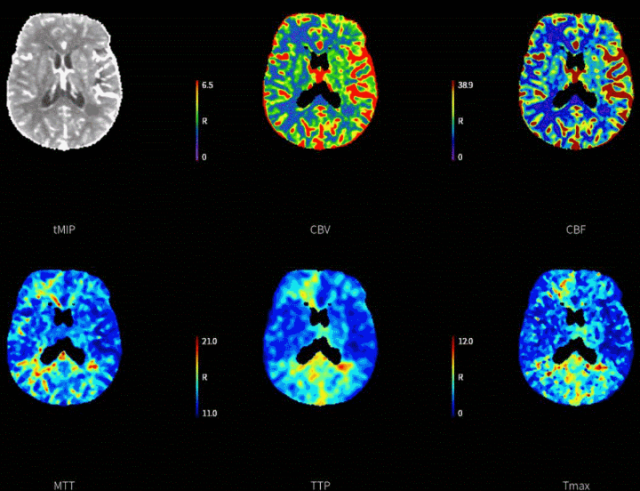

脑动脉CTA提示:左侧颈内动脉、大脑中动脉显影均较对侧显影明显变淡;后循环纤细。CTP提示:左侧额顶颞叶大片状低灌注区域,mismatch体积134ml,mismatch比值7.0。结合症状及影像学评估,左侧颈内动脉为导致缺血症状的病变血管。

此患者症状进行性加重,CTP提示:左侧额顶颞叶大片状低灌注区域,mismatch体积134ml,mismatch比值7.0,考虑ICAS病变可能性大,血栓负荷小,无需大口径抽吸导管。